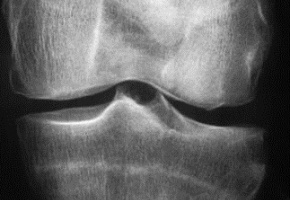

[CONGRES DE L'EULAR] Le congrès de la Ligue européenne contre les rhumatismes (Eular), qui s’est déroulé à Madrid du 12 au 15 juin 2019, a confirmé que, dans l’arthrose, la recherche de traitements se poursuit, alors que le nombre de médicaments disponibles se réduit. Divers agents modifiant le métabolisme osseux ou cartilagineux, limitant la douleur ou l’inflammation, sont en développement.   Trouver de nouvelles solutions thérapeutiques est indispensable dans l’arthrose. La maladie connait en effet un développement considérable dans le monde, ce qui est source d’une charge croissante pour la société. En outre, il s’agit d’une maladie sérieuse qui s’associe à un excès de mortalité, notamment cardiovasculaire en comparaison de la population générale, a rappelé le Pr Francis Berenbaum (Hôpital Saint-Antoine, AP-HP, Paris). Une étude américaine conduite à partir d’analyses de squelettes a, par exemple, observé que 8 % des individus de plus de 50 ans présentaient des signes de gonarthrose à la période préhistorique (6000-300 before present), 6 % à la période pré-industrielle (1800-1900) et 16 % depuis la période post-industrielle (fin des années 1900 au début des années 2000) (1). "Ce doublement de prévalence de l’arthrose met probablement en cause d’autres facteurs liés à l’environnement que l’obésité et qu’il faudra identifier", a indiqué le Pr Berenbaum. Que faire ? En premier lieu, proposer les traitements non pharmacologiques tels qu’exercice, réduction du poids, aide à la marche au besoin avec des dispositifs techniques. Les recommandations de l’Eular (qui concernent aussi les patients avec une polyarthrite rhumatoïde (PR) ou un rhumatisme psoriasique) préconisent en cas de gonarthrose ou de coxarthrose la pratique d’exercices contribuant à améliorer santé cardiorespiratoire, force musculaire, souplesse et performances neuromotrices (2).   Peu de moyens médicamenteux Sur le plan médicamenteux, "les moyens disponibles sont de moins en moins nombreux", a admis le Pr Berenbaum.  De fait, une méta-analyse Cochrane (10 essais randomisés, 3541 patients), publiée en février 2019, a conclu que l’efficacité antalgique et fonctionnelle du paracétamol (pourtant conseillé en 1e ligne dans toutes les recommandations internationales) est faible (3). Une étude danoise réalisée à partir de 252 études de cohorte nationales a aussi suggéré que les anti-inflammatoires non stéroïdiens oraux (préconisés en 2e ligne) exposent non seulement à un risque cardiovasculaire accru au long cours, comme on le suspectait depuis longtemps, mais que le diclofénac pourrait majorer de 20 à 80 % à court terme la probabilité de survenue d’événements cardiovasculaires (4). En septembre 2018, l’ANSM a d’ailleurs rappelé aux prescripteurs français d’AINS la nécessité "d’évaluer au préalable les risques cardiovasculaires du patient" et "d’administrer les doses les plus faibles possibles et pour la durée la plus courte possible". En mars 2019, c’est le tramadol qui était à son tour visé avec la publication d’une étude décrivant un excès de mortalité (en comparaison des AINS) chez les patients arthrosiques de plus de 50 ans ayant pris cet antalgique (5). Dans ce contexte décourageant, "les améliorations ne peuvent venir que de l’innovation", a considéré le Pr Berenbaum. Fort heureusement, quelques cibles d’action ont été identifiées qui reposent sur le freinage du catabolisme osseux (voie WNT, cathepsine K), ou cartilagineux (inhibiteurs de métalloprotéases), l’activation de l’anabolisme ou la régénération du cartilage. "Pour le moment, agir sur l’inflammation en inhibant l’interleukine 1 a été un échec mais la cytokine ciblée n’était peut-être pas la bonne." Un essai de phase 2 b de 24 semaines, présenté en octobre 2018 par le Dr Yusuf Yazici (San Diego, États-Unis), lors du congrès de l’American College of Rheumatology, a rapporté des résultats intéressants sur le plan fonctionnel dans la gonarthrose, après injections intra-articulaires de lorecivivint, un inhibiteur de la voie WNT impliquée dans le catabolisme osseux. Le MIV-711, un inhibiteur sélectif de la cathepsine K, semble aussi prometteur. Le développement de la sprifermine est, quant à lui, "plus avancé". Cette molécule, qui active la production de cartilage par les chondrocytes en activant les récepteurs du fibroblast growth factor (FGF), a montré dans des résultats préliminaires de l’essai de phase 2 de 2 ans Forward, un effet structural dans la gonarthrose. La médecine régénérative, qui fait le buzz sur la toile, se développe aussi avec les injections de cellules mésenchymateuses, dont on espère qu’elles auront la capacité de se transformer en chondrocytes fabriquant du cartilage ou de sécréter des molécules anti-inflammatoires ou freinant les processus de dégradation osseuse. Une méta-analyse a conclu à la sécurité de cette stratégie thérapeutique et à ses effets positifs pour améliorer à 1 an scores de douleur et de fonction articulaire dans la gonarthrose (6). "Mais cela reste à vérifier dans un essai randomisé rigoureux", a insisté le Pr Berenbaum. C’est d’ailleurs l’objectif de l’étude Adipoa-2, qui va comparer en double aveugle chez 153 patients, suivis 25 mois, injection dans le genou de cellules mésenchymateuses (à 2 doses) et placebo.   Une biothérapie antalgique Enfin, la lutte contre la douleur reste essentielle dans l’arthrose ; "20 % des patients avec une prothèse de genou continuent de se plaindre de douleurs chroniques". Le nerve growth factor (NGF), une neurotrophine qui intervient dans la transduction du signal douloureux semble être une bonne cible. L’analyse de plusieurs études cliniques de phase 3 contrôlées contre placebo, menées dans la gonarthrose ou la coxarthrose, vient de confirmer que le tanézumab, un anticorps monoclonal humanisé dirigé contre le NGF, a une efficacité intéressante contre la douleur arthrosique (8). Cependant, étant donné un risque certes faible mais significatif d’arthrose rapidement progressive (1 à 3% des patients traités), liée probablement au fait que les patients ne ressentent plus la douleur, "la question sera de savoir à quels patients proposer en priorité cette biothérapie, que l’on administre sous la forme d’injections sous-cutanées toutes les 8 semaines".     1 - Wallace IJ, et al. Proc Natl Acad Sci U S A. 2017;114:9332-9336. 2 - Rausch Osthoff A.K, et al. 2018 EULAR recommendations for physical activity in people with inflammatory arthritis and osteoarthritis. Ann Rheum Dis. 2018;77: 1251-1260. 3 - Leopoldino AO, et al. Cochrane Database of Systematic Reviews 2019, Issue 2. Art. No.: CD013273. 4 - Schmidt M, et al. BMJ 2018;362:k3426. 5 - Zeng C, et al. JAMA. 2019;321:969-982. 6 - Yubo M, et al. PLos One 2017.12(4): e0175449. 7- Tive L, et al. J Pain Res. 2019;12:975-995.

La prednisolone efficace dans l’arthrose digitale

L’étude randomisée en double aveugle, Hope, menée chez 92 patients (dans 79 % des femmes) avec une arthrose des mains sévère s’accompagnant de synovite, suggère qu’une corticothérapie à faible dose permet de soulager une poussée inflammatoire douloureuse. Les patients ayant reçu 10 mg/j de prednisolone durant 6 semaines présentaient, en effet, un score de douleur nettement plus faible que les patient mis sous placebo (-16,5 points pour l’échelle visuelle analogique). Ce traitement a été bien toléré "et la fonction articulaire s’est significativement améliorée sous celui-ci (p = 0,01), de même que la qualité de vie", a rapporté le Dr Féline Kroon (Centre médical universitaire de Leiden, Pays-Bas). A 12 semaines, après arrêt (sur 2 semaines) de la corticothérapie, la différence avait néanmoins disparu entre les 2 bras.